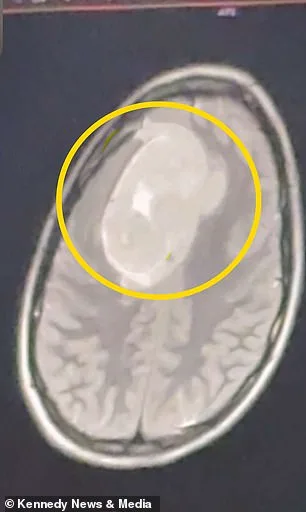

Keating, who had never experienced headaches before in her life, found herself questioning everything. Her symptoms worsened during Christmas break, forcing her to confront a reality no one expected: she was no longer just a student struggling with finals. She was a patient facing a mystery no one could solve. When she returned to her second doctor, they ordered an MRI—a decision that felt like a miracle. By January 2026, the scans revealed a tumor the size of a tennis ball nestled in her left frontal cortex. That area of the brain, responsible for executive function and language, was under siege. The discovery upended her life, but the real question lingers: How many other patients have been misdiagnosed or ignored, their pain reduced to a 'stress' label?

The tumor, though benign, posed a silent threat. Doctors said it had been growing for years, pressing slowly but relentlessly against critical brain tissue. Without intervention, it could have caused irreversible damage—changes in personality, cognitive decline, or motor impairments. Keating's journey from college student to surgical patient was not just a personal tragedy but a stark reminder of the risks of delayed care. What if she had not pushed for answers? What if another young person faced the same fate, unaware their body was sending urgent signals?